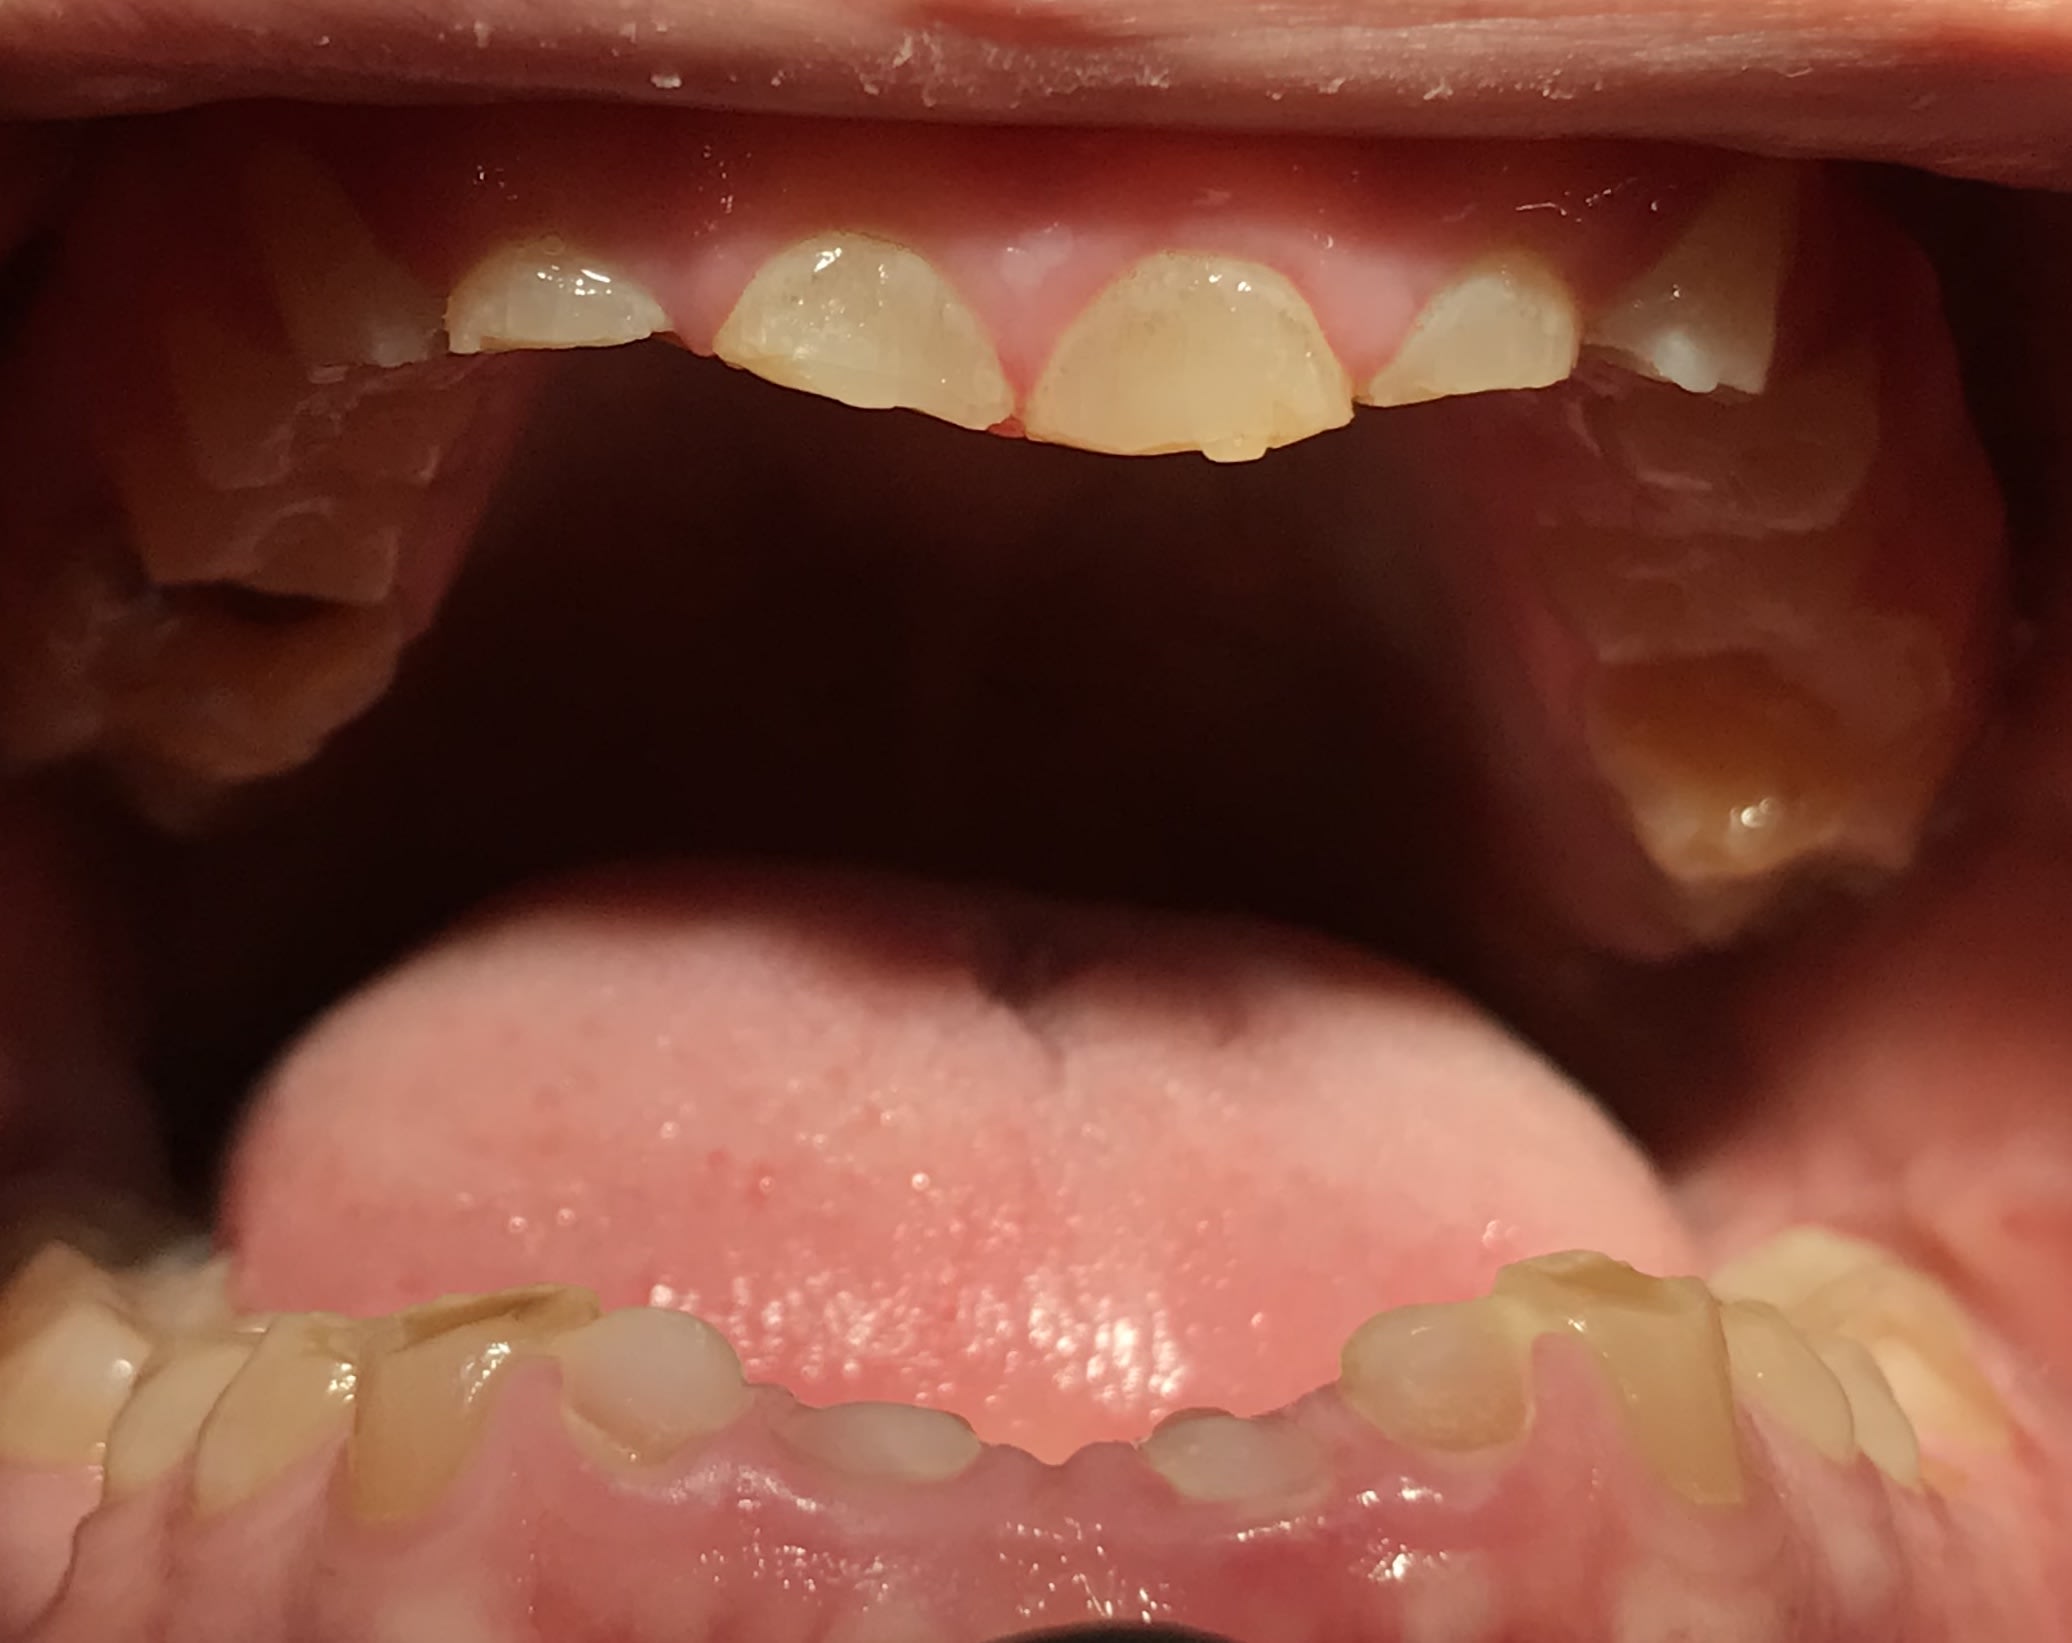

Photos

9db1a8f8 0abe 44f7 87a9 75959bc99136 uojbwk - Eugenol

E2f69a8e 1293 4d24 bc42 b326036451b8 xx21g7 - Eugenol

40edc7b8 ac35 4fb0 a890 d3676a6f086c zc7npz - Eugenol

F210636b b920 48ee 9616 3728267b0311 w3y9lx - Eugenol